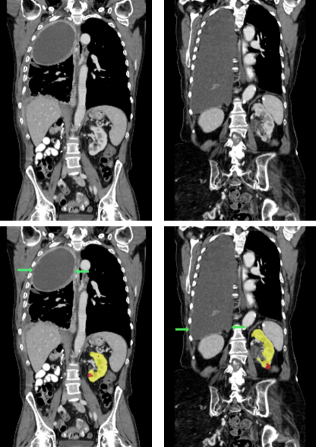

Figure 3: Four examples of CT scans from the training set (dataset A) showing coronal sections with annotations in format 2 (see Figure 2(c)) where yellow and red overlays represent annotations of the parenchyma and kidney abnormalities, respectively. Note that all the patients have anomalies in the body (green arrows in the body), and both cases of (b) have only one kidney and contain kidney abnormalities. All the slices have a window center of 60 HU and a window width of 360 HU.

Samples of CT scans from patients included in this study can be seen in Figure 3. While Figure 3(a) depicts patients without kidney abnormalities, it highlights the presence of abnormalities in other parts of the body, such as liver tumors. Figure 3(b) shows patients with kidney abnormalities, as well as other abnormalities in the body, such as nephrectomy and collapsed lung.